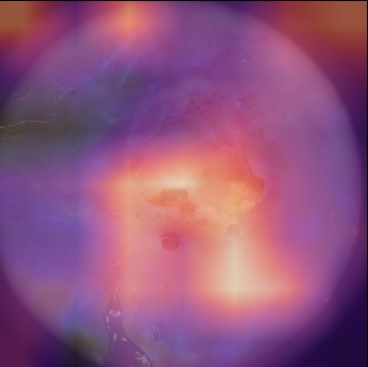

State-of-the-art deep learning approaches for skin lesion recognition often require pretraining on larger and more varied datasets, to overcome the generalization limitations derived from the reduced size of the skin lesion imaging datasets. ImageNet is often used as the pretraining dataset, but its transferring potential is hindered by the domain gap between the source dataset and the target dermatoscopic scenario. In this work, we introduce a novel pretraining approach that sequentially trains a series of Self-Supervised Learning pretext tasks and only requires the unlabeled skin lesion imaging data. We present a simple methodology to establish an ordering that defines a pretext task curriculum. For the multi-class skin lesion classification problem, and ISIC-2019 dataset, we provide experimental evidence showing that: i) a model pretrained by a curriculum of pretext tasks outperforms models pretrained by individual pretext tasks, and ii) a model pretrained by the optimal pretext task curriculum outperforms a model pretrained on ImageNet. We demonstrate that this performance gain is related to the fact that the curriculum of pretext tasks better focuses the attention of the final model on the skin lesion. Beyond performance improvement, this strategy allows for a large reduction in the training time with respect to ImageNet pretraining, which is especially advantageous for network architectures tailored for a specific problem.